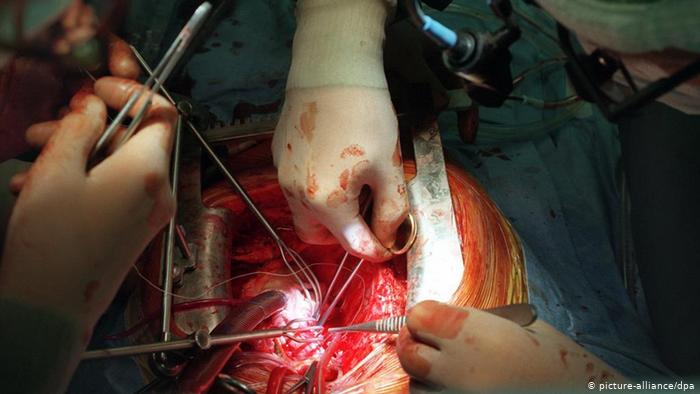

صمامات اصطناعية للقلب

في حال تعطل صمامات القلب عن عملها الطبيعي أو في حال تآكلها يستعمل الأطباء بدلا عنها مواد بيولوجية بديلة مستخرجة من الخنازير أو صمامات معدنية. وفي الوقت الحاضر توجد أيضا صمامات اصطناعية صغيرة قابلة للامتداد، كما يظهر في الصورة، ويتم ربطها بقلب المريض عن طريق عملية القسطرة.